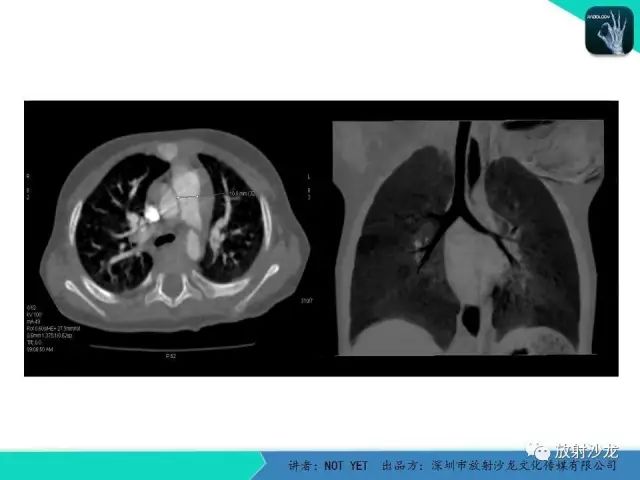

【病例】动脉导管未闭1例CT影像表现